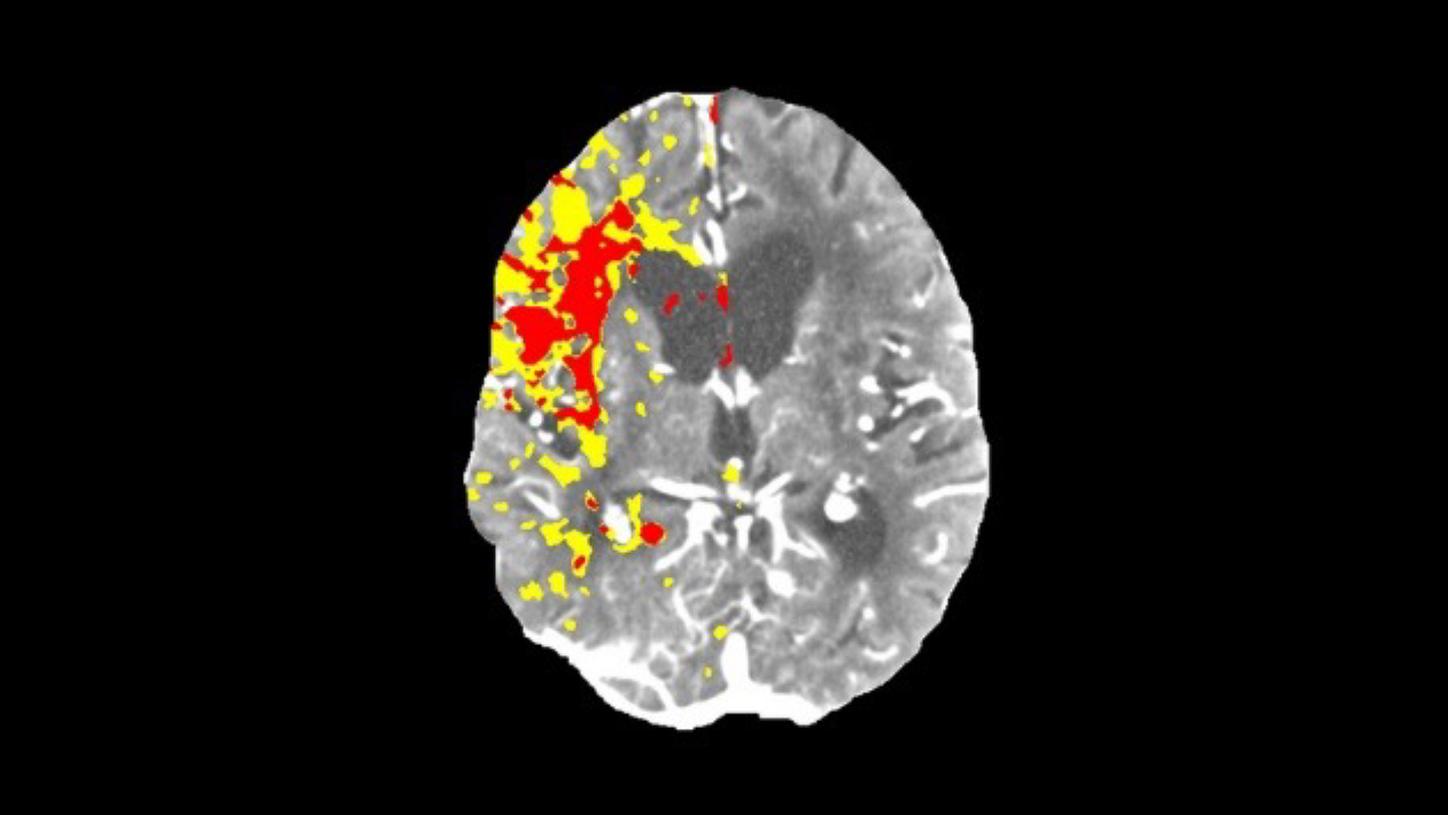

Perfusion scan

Evaluation of infarct core and penumbra by automatically providing perfusion maps for further treatment decisions